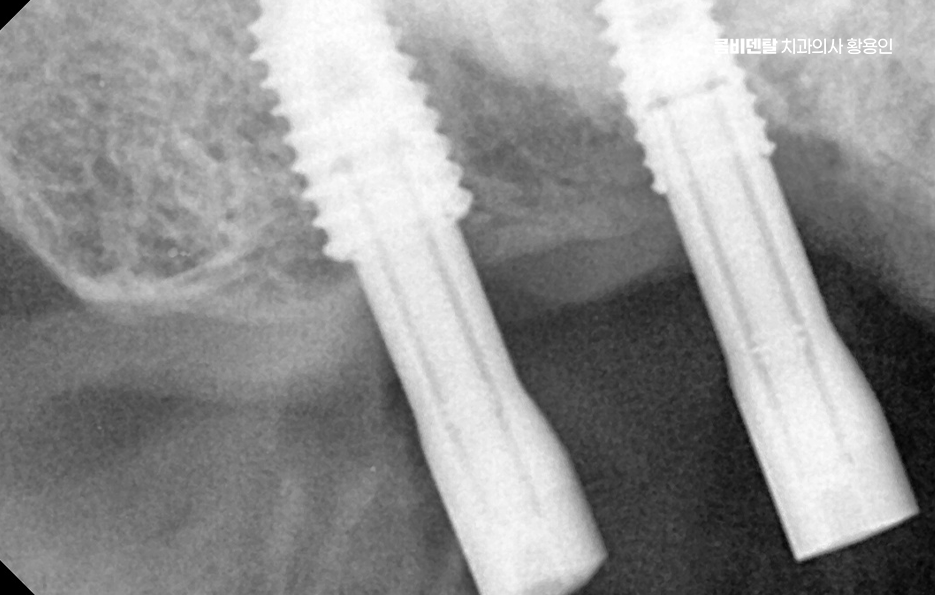

그래서 이런 문제들을 막기 위해서라도 임플란트는 어금니 상실 후 중요한 치료 옵션으로서 임플란트는 빠진 치아의 뿌리 역할까지 해주기 때문에, 단순히 공간을 채우는 게 아니라 턱뼈에 자극을 줘서 뼈 흡수를 막아주고, 위아래 치아가 정상적으로 맞물릴 수 있게 해주며 다른 보철 방식과 비교해도 장기적인 안정성과 기능 회복 면에서 유리한 거예요.

임플란트를 빨리 하는 게 좋은 이유는, 시간이 지나면서 턱뼈가 점점 흡수돼버리면 임플란트를 심을 뼈 자체가 부족해지는 상황이 생기기 때문이며 이때는 뼈이식이나 상악동 거상술 같은 추가 수술이 필요하게 되고, 치료 기간도 길어지고, 비용도 많이 올라가기 때문에 어금니가 빠졌다고 방치하는 시간만큼 치료는 더 복잡해질 수 있다는 점에서 어금니 없으면 얼굴 발음 및 오늘 알아본 것처럼 다양한 문제로 이어질 수 있음을 잘 이해하여 빠르고 나에게 맞는 치료 계획을 세우시고 장기적으로는 수명 유지까지 잘 고려하여 치료 계획을 잘 세워보시길 바라고 있어요